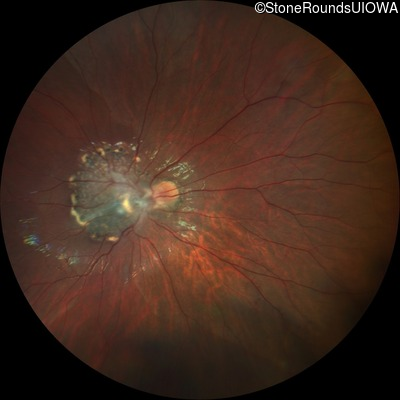

This 9 year old male was noted to have some crossing of his eyes at 2 months of age and the eye exam which followed identified a retinal lesion in the right eye. When he was six years old an epiretinal membrane was noted in his left eye. Two years later it was decided that it was a thin hamartoma in that eye as well. He underwent neuroimaging at age 7 which identified bilateral acoustic neuromas.

| Age at visit: 8 years |

| Age at visit: 10 years |

| Age at visit: 11 years |

| Age at visit: 14 years |